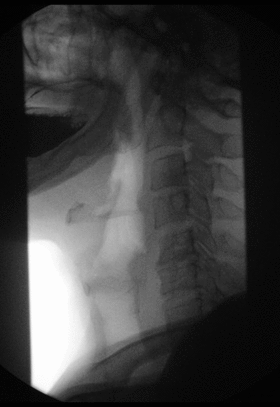

A barium swallow exam taken via fluoroscopy.

Another common procedure is the modified barium swallow study during which barium-impregnated liquids and solids are ingested by the patient. A radiologist records and, with a speech pathologist, interprets the resulting images to diagnose oral and pharyngeal swallowing dysfunction. Modified barium swallow studies are also used in studying normal swallow function.

Fluoroscopy can be used to examine the digestive system using a substance which is opaque to X-rays (usually barium sulfate or gastrografin), which is introduced into the digestive system either by swallowing or as an enema. This is normally as part of a double contrast technique, using positive and negative contrast. Barium sulfate coats the walls of the digestive tract (positive contrast), which allows the shape of the digestive tract to be outlined as white or clear on an X-ray. Air may then be introduced (negative contrast), which looks black on the film. The barium meal is an example of a contrast agent swallowed to examine the upper digestive tract. Note that while soluble barium compounds are very toxic, the insoluble barium sulfate is non-toxic because its low solubility prevents the body from absorbing it.